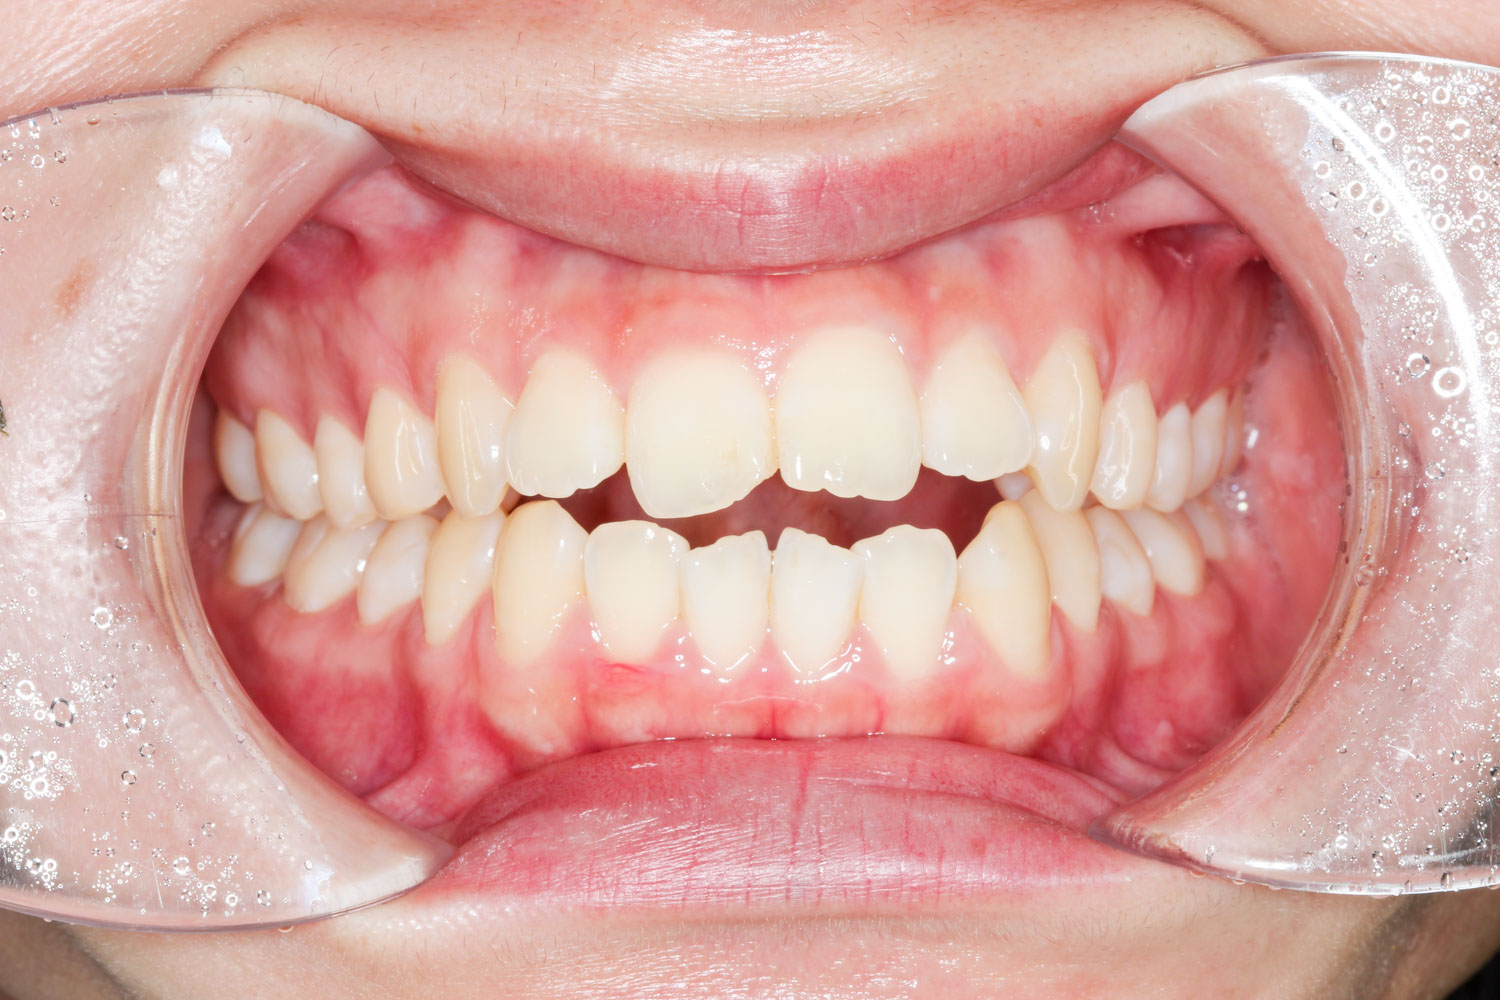

Before

After

年齢 10代

治療装置 上下とも裏側の矯正装置(フルリンガル)

治療内容 非抜歯

治療期間 2年8か月

リスク 歯の移動に伴う痛み、歯肉退縮、歯根吸収、歯肉炎、虫歯

主訴 八重歯が気になる

症状 叢生(ガタガタ)

治療回数 35回程度

総額費用 140万円程度